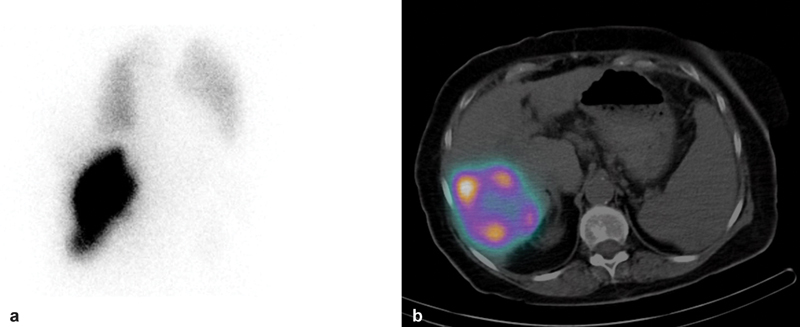

MAA SPECT/CT Scan

Treatment Day

• Post-treatment SPECT or PET imaging